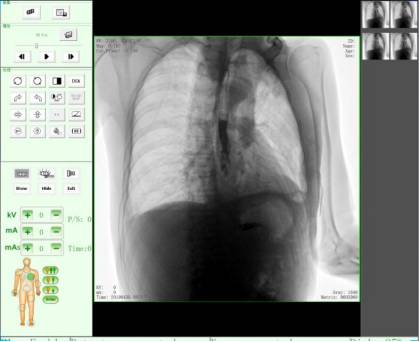

二、人體圖形化的操作界面

醫生可根據人體圖形化操作界面直觀快速的選取拍攝部位和設置參數,較下拉式的部位選擇更加節約時間、確保優質的客戶體驗感。

三、實時圖像處理功能

在圖像采集過程中可以對圖像做各種軟件功能鍵的處理,快速呈現醫生閱片所需功能的對應圖像。